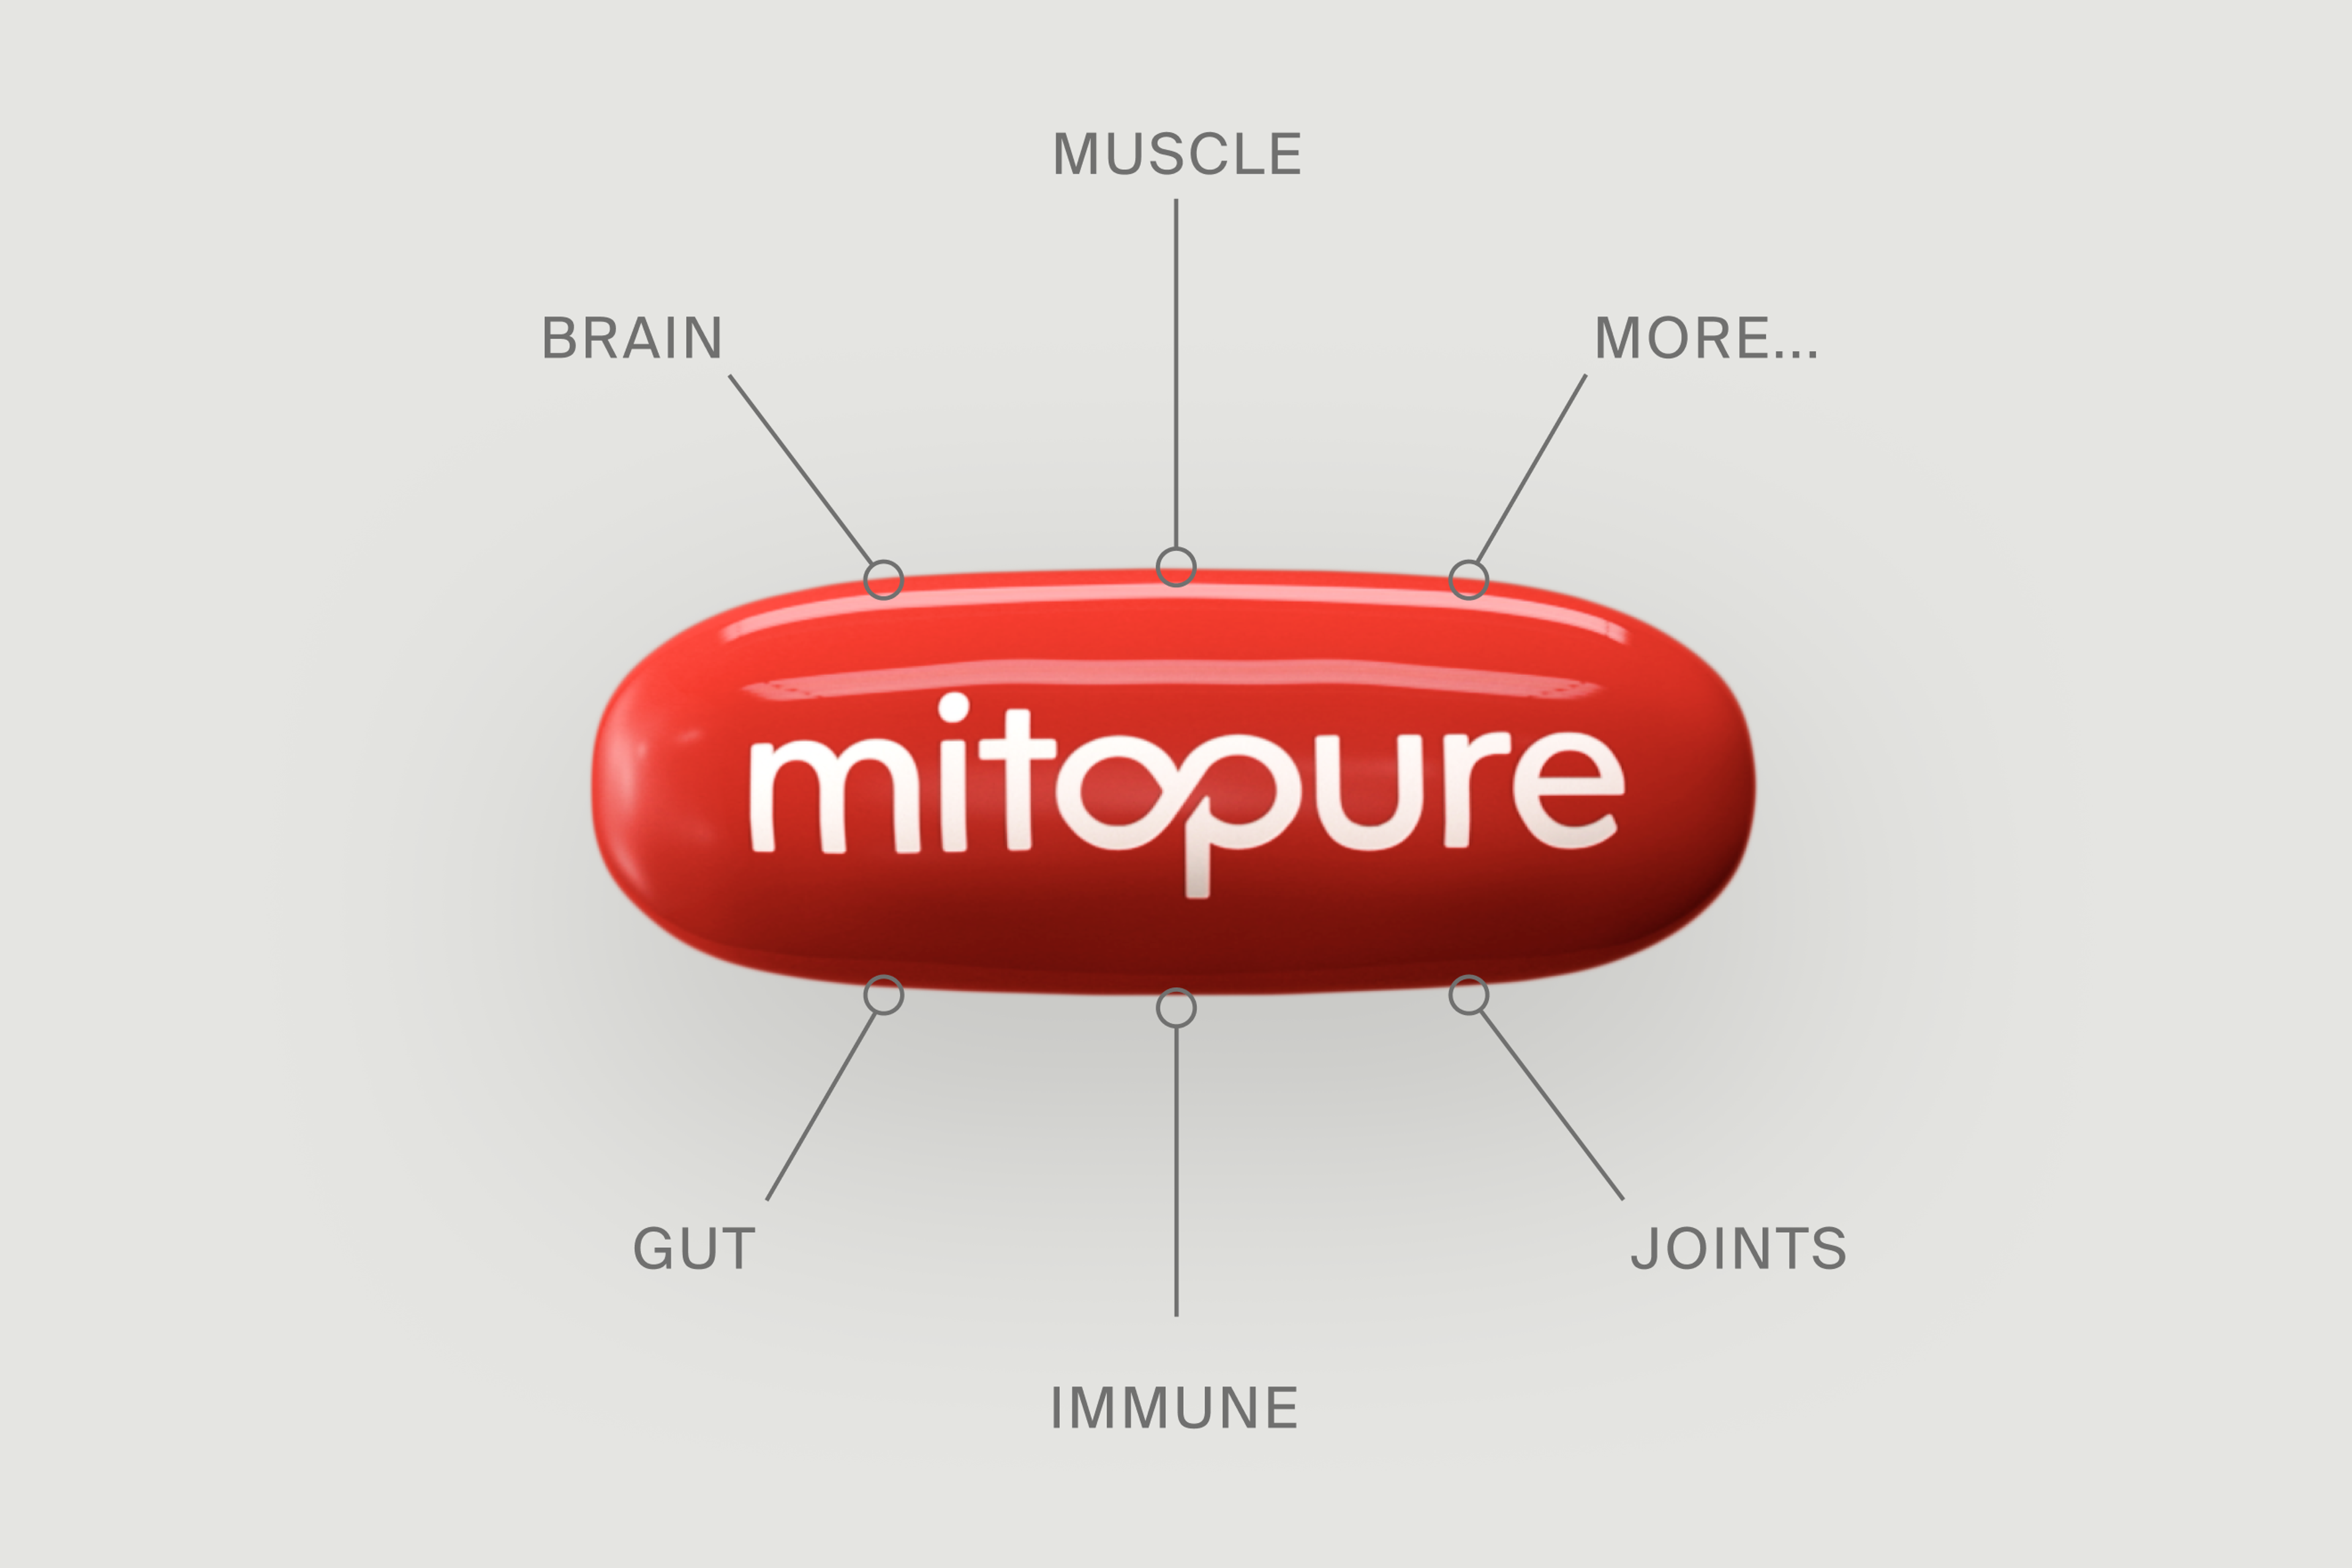

There are over 300 published pre-clinical and clinical trials examining the health benefits of Urolithin A (Mitopure), with a peak of publications coming out in 2022. This makes Mitopure one of the most researched longevity supplements on the market.

Pioneering, cutting-edge research has been at the core of our company since its inception over a decade ago. For many years we were leading the charge on Urolithin A research largely on our own, but that is no longer the case, as we're now seeing a wave of interest from leading labs around the world. This year we published two human trials, and across the globe, top-level research institutions conducted numerous pre-clinical trials examining the diverse potential applications of Urolithin A, including brain health and neuroprotective benefits, the immune system, joints, and reproductive health.